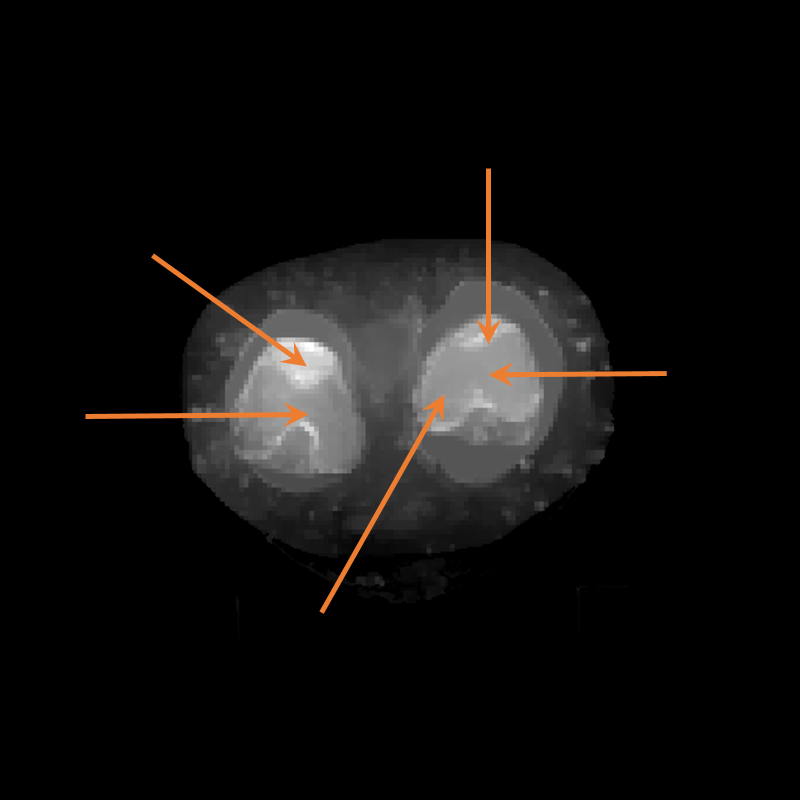

Figure 3: Visualization of axial frames of a mummy [6] selected in proximity of the thigh. (a) Some of the regions we are interested to segment are indicated. (b) Artifacts caused by presence of metals.

In Fig. 3a, we show one axial slice of a male mummy with indication of the regions to be segmented. Fig. 3b illustrates that metals present inside a bandaged mummy generate severe artifacts, which are not present in standard biomedical data.